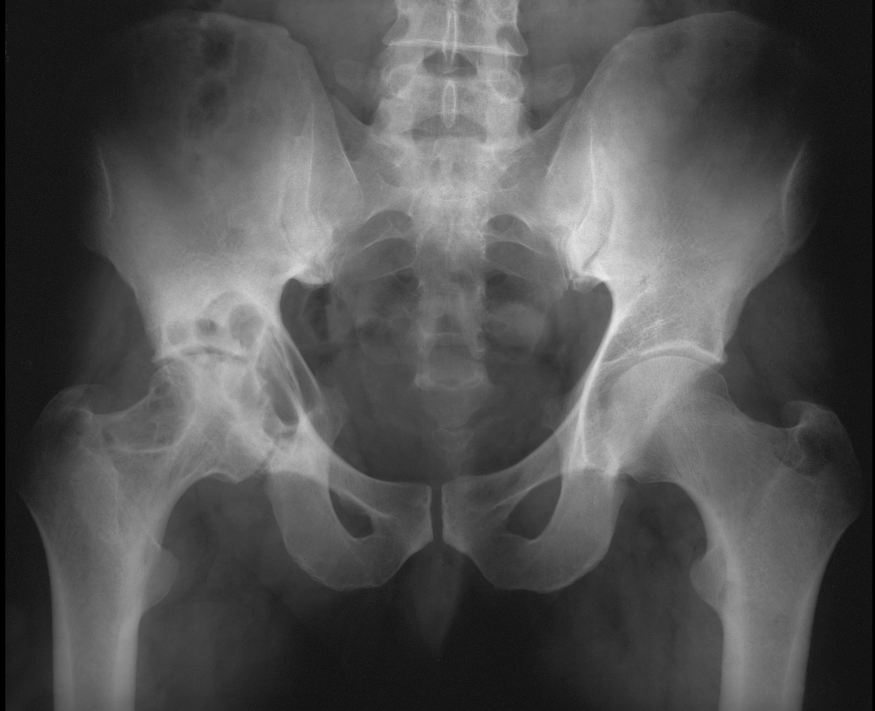

Sites for degenerative changes in the SI joints

What to consider for a monoarticular arthritic process in an elderly man?

Gout